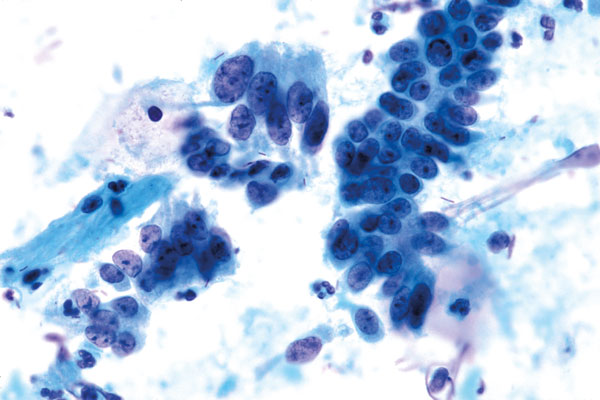

c. Zervikales Adenokarzinom (V-g)

- Lockere, verbandartige Lagerung

- deutlich größere Kerne als bei normalen Endozervikalzellen

- Zellen nicht wesentlich größer normale Endozervikalzellen

- Hyperchromasie, aber häufig feines Chromatin

- Auffällige Nucleolen